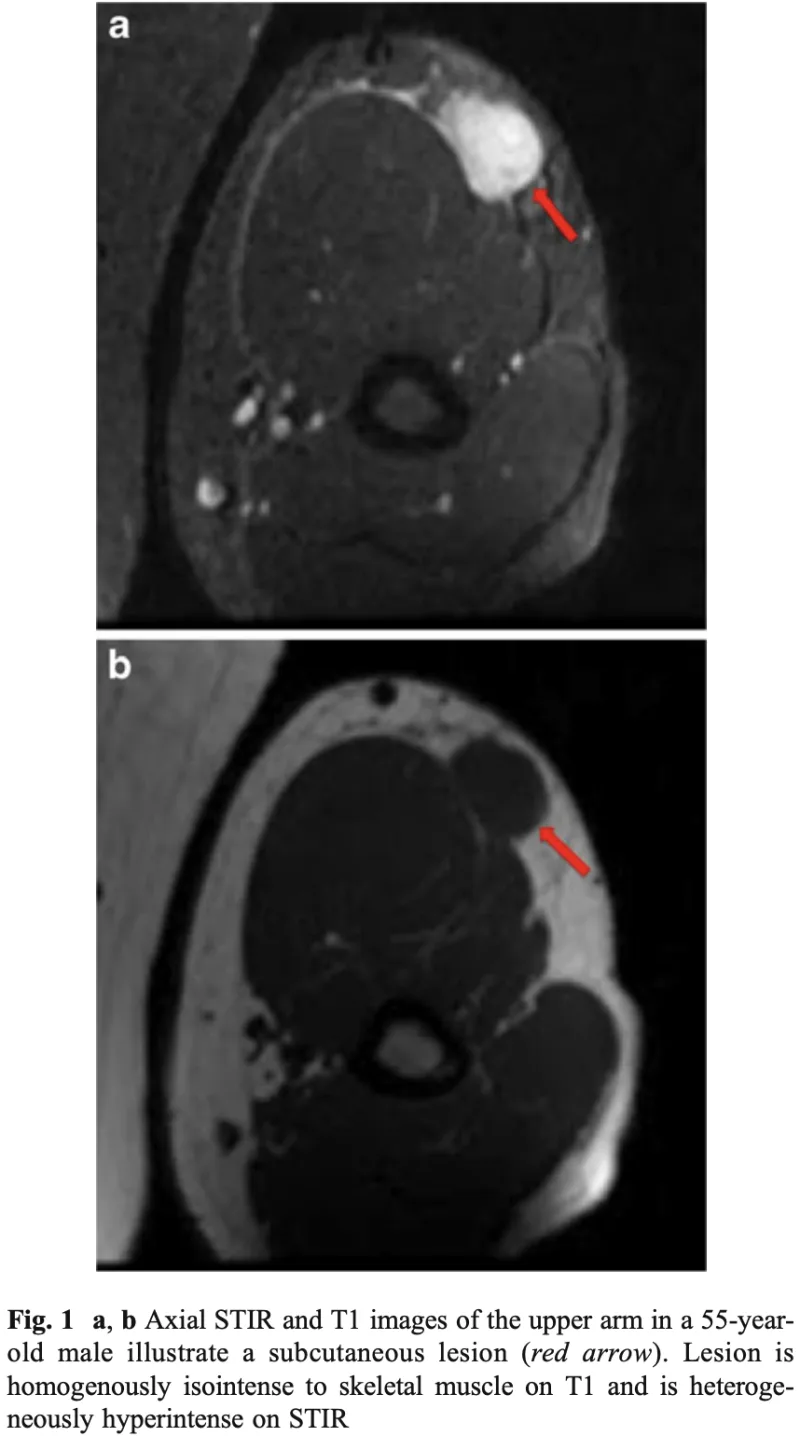

結節性筋膜炎の患者

先輩医師の整形外科クリニックからすねに腫瘤を生じた若年成人の患者さんが紹介されて受診.

すねの皮下脂肪の中に, 2 cmくらいのしこりを触知.

造影MRIを撮像して, 診断することにしました.

皮下脂肪の深部に丸い腫瘤を認めます.

造影MRIの結果, すねの皮下脂肪の深部にある浅筋膜に造影効果のある2 cm弱大の腫瘍を認め, 結節性筋膜炎が強く疑われました.

『結節性筋膜炎』は, 『筋膜炎』という名前がついていますが, 良性の軟部腫瘍のひとつです.

皮下組織や筋膜から発生し, 若年成人(20~50歳代)に多い良性の線維性腫瘍様病変です.

数週間で急速に大きくなり, 痛みや圧痛を伴うことが多く, 前腕や体幹に好発します.

通常, 3 cm以下で, その後自然に小さくなり, 消失します.

悪性の軟部腫瘍と見分ける必要があるので, 厳重に経過を観察して, 3 cmを超えて大きくなる場合には, 生検を行う方針としました.